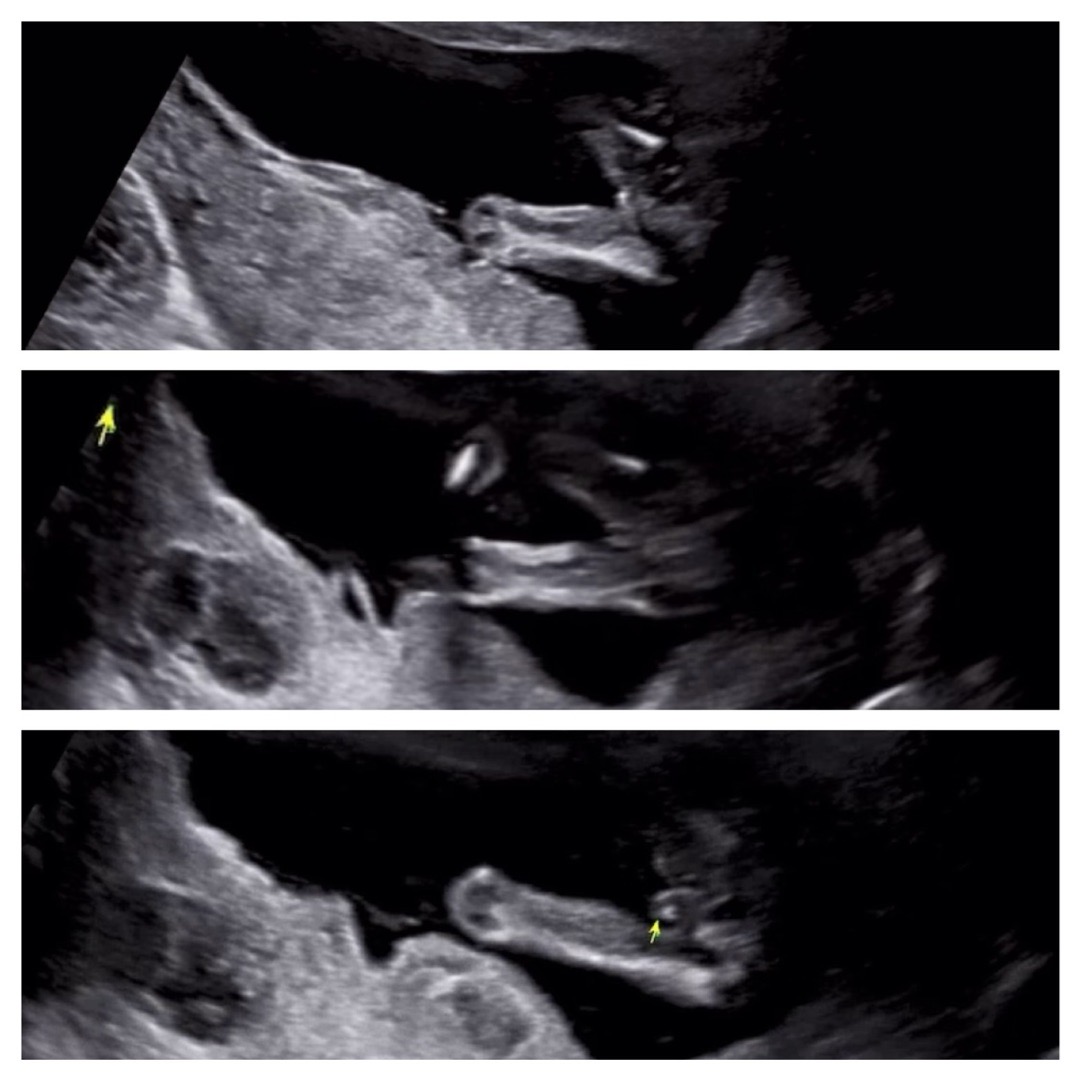

15주 이정도면 확실하쥬? ㅎ

🍑90프로라고 하셨는데 반전 없겠죠???